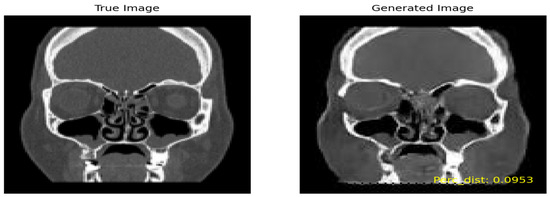

Similarly, for the ‘Severe’ class, an SSIM threshold of 0.475 and higher was employed to preserve the generated images with the utmost similarity to the true images. Among the 693,079 combinations considered, 703 images surpassed the 0.6 similarity threshold and were chosen for further analysis. Figure 9 shows the true image on the left and the generated image on the right by including high perceptual similarity.

• Perceptual Similarity

Following a similar methodology as employed for the SSIM, we conducted a thorough similarity assessment using the perceptual metric. For the ‘Moderate’ class, with an initial pool of 852,640 combinations, 1523 images were generated, adhering to a threshold of 0.175. In the case of the ‘Severe’ class, involving 693,079 combinations, a set of 1665 images was generated, applying a threshold of 0.2035.

Figure 9. Comparison of true and generated images with perceptual similarity.